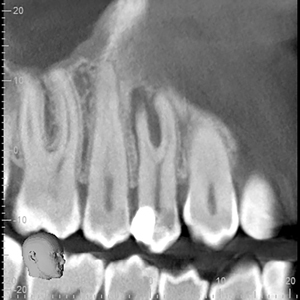

Many of our patients are attracted to the allure of cheaper dental treatment abroad. Tooth #36 in the accompanying radiograph (Fig. 1) and photo (Fig. 2) is an example of such a case. Unfortunately in this case, almost every possible iatrogenic endodontic mishap was encountered. This treatment is substandard and if done in Canada the … Read more